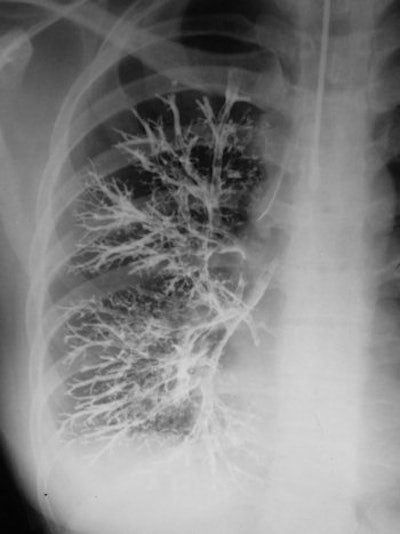

Bronchography

In bronchography, the bronchial tree was opacified with an opaque medium using a variety of techniques. In the illustration below, a catheter was used with contrast injected. The examination shows a normal right bronchogram. The examination was unpleasant for the patient, and there was therefore a high threshold of referral for performing the examination. The chest physician would be reluctant to submit the patient for the procedure unless there was a degree of confidence about the examination.

In bronchography, a catheter was used with contrast injected to examine the bronchial tree.The introduction of high-resolution CT (HRCT) has considerably changed attitudes about bronchiectasis. Because so many more patients are examined than were possible with bronchography, it is now known that bronchiectasis is much more common than physicians had previously appreciated. The first experimental bronchogram was performed by Karl Springer from Prague in 1906, which is surprisingly early. Over the years, the technique used many contrast agents, including colloidal silver and bismuth. In classical brochography, iodized oil was used, commonly introduced by tracheal injection. Contrast could also be introduced using a catheter, bronchoscope, or dripped over the back of the tongue.